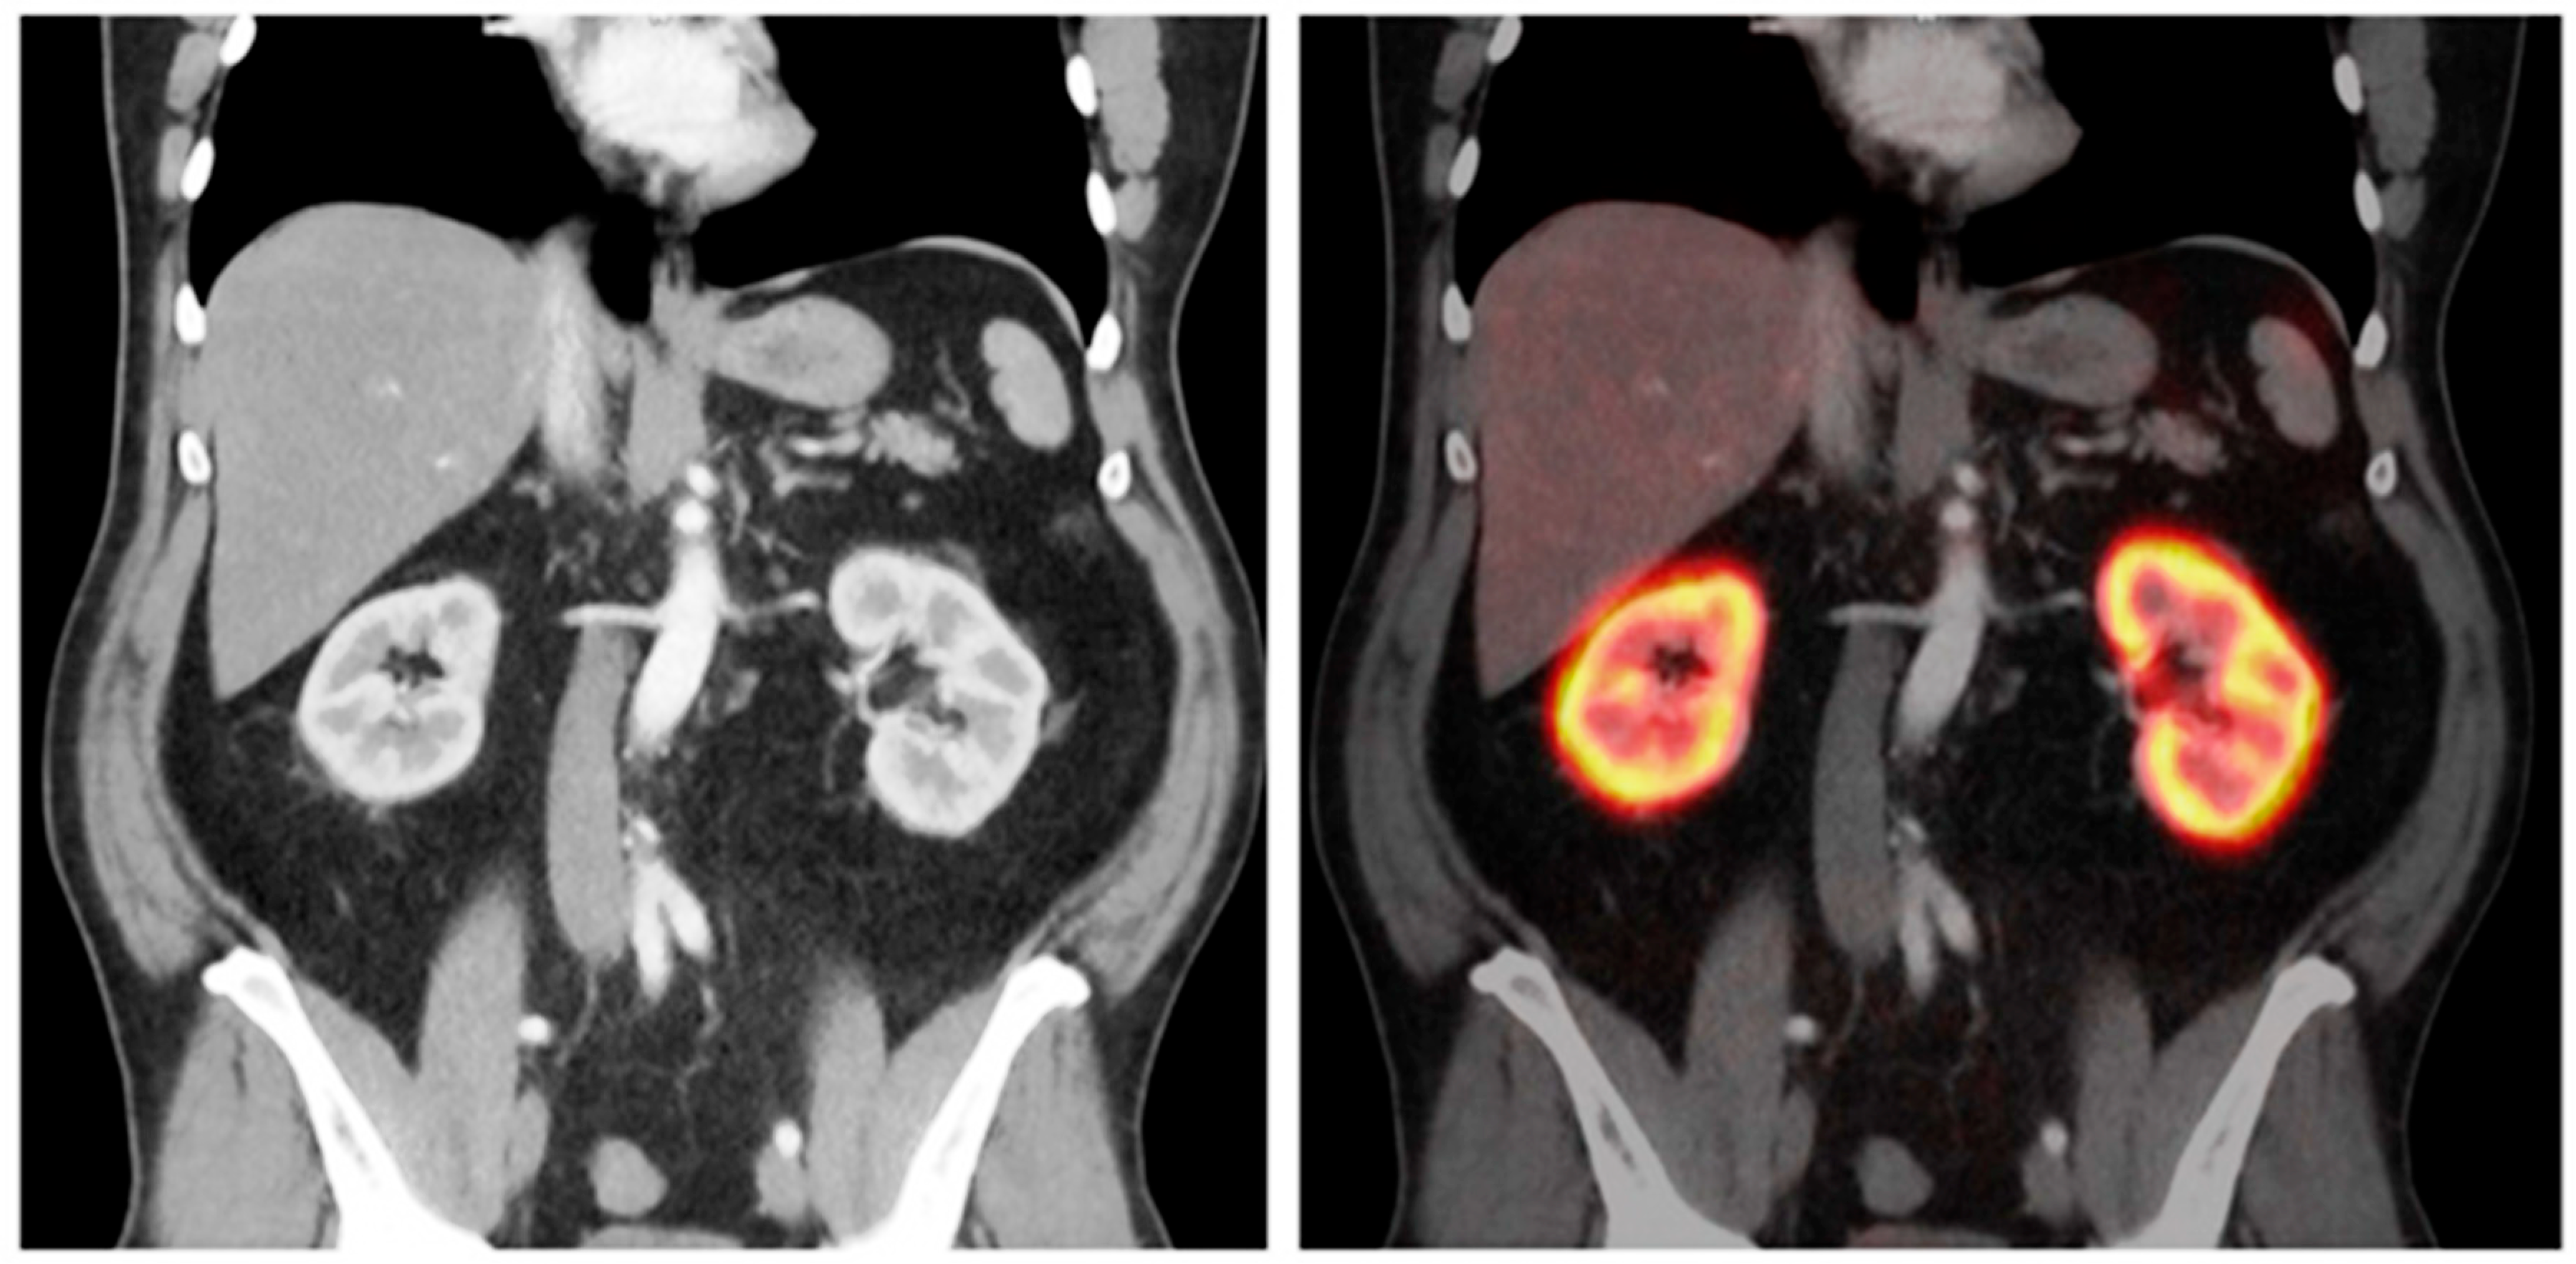

4.1.1. 68Ga-EDTA

| 68Ga-EDTA | Gallium-68 | Stable metal chelate, low protein binding, exclusive glomerular filtration | Strong correlation with reference 51Cr-EDTA clearance (r = 0.94), suitable for split renal function assessment | High spatial/temporal resolution, 3D quantification, low radiation dose | Underestimates GFR >150 mL/min, scarce large prospective validation |